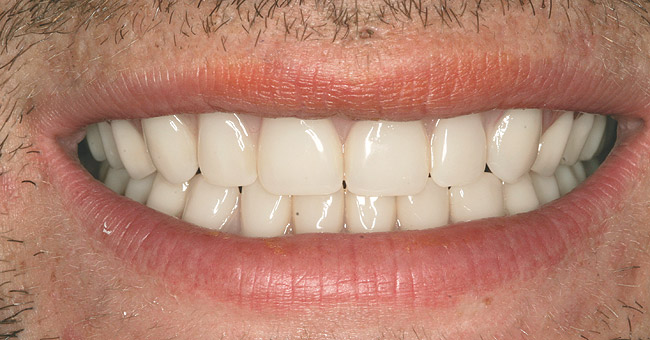

As a new patient, Joe was instantly likable. He had a great sense of humor. He regretted how his life had turned out. When he finally presented to this author’s practice he was 24 years old. He wanted to remove the evidence of his addiction that were visible to anyone that came in contact with him. His teeth were totally destroyed by his drug use. There was no hope of saving any of them. There were horrible infections in his jaw bones that were spreading through his system. His only option was to remove all of his teeth and have dentures made. Impressions were taken with alginate. A bite was established in maximum intercuspation. We decided that his preoperative incisal edge positions of teeth Nos. 9 and 10 were adequate to recreate the incisal edge position in full dentures.

After his treatment was complete (Figure 7 and Figure 8), Joe wrote a letter to convey his gratitude. In part, it said:

I just wanted to say thank you for this opportunity that has really helped me in ways unimaginable. Now I can look in the mirror and see myself as I used to look before my addiction took hold of me. I now hold my head up proudly. I am no longer self-conscious about how I look and I have been clean for almost 2 years. With my new teeth, I now look clean as well. People look at me differently, and they treat me like I am a normal person! I feel whole. Thank you for my smile. You have changed my life!

Figure 7  FINAL RESULTS Completing dental treatment gave Joe a newfound sense of self-esteem.

Figure 7

Figure 8  FINAL RESULTS Completing dental treatment gave Joe a newfound sense of self-esteem.

Figure 8